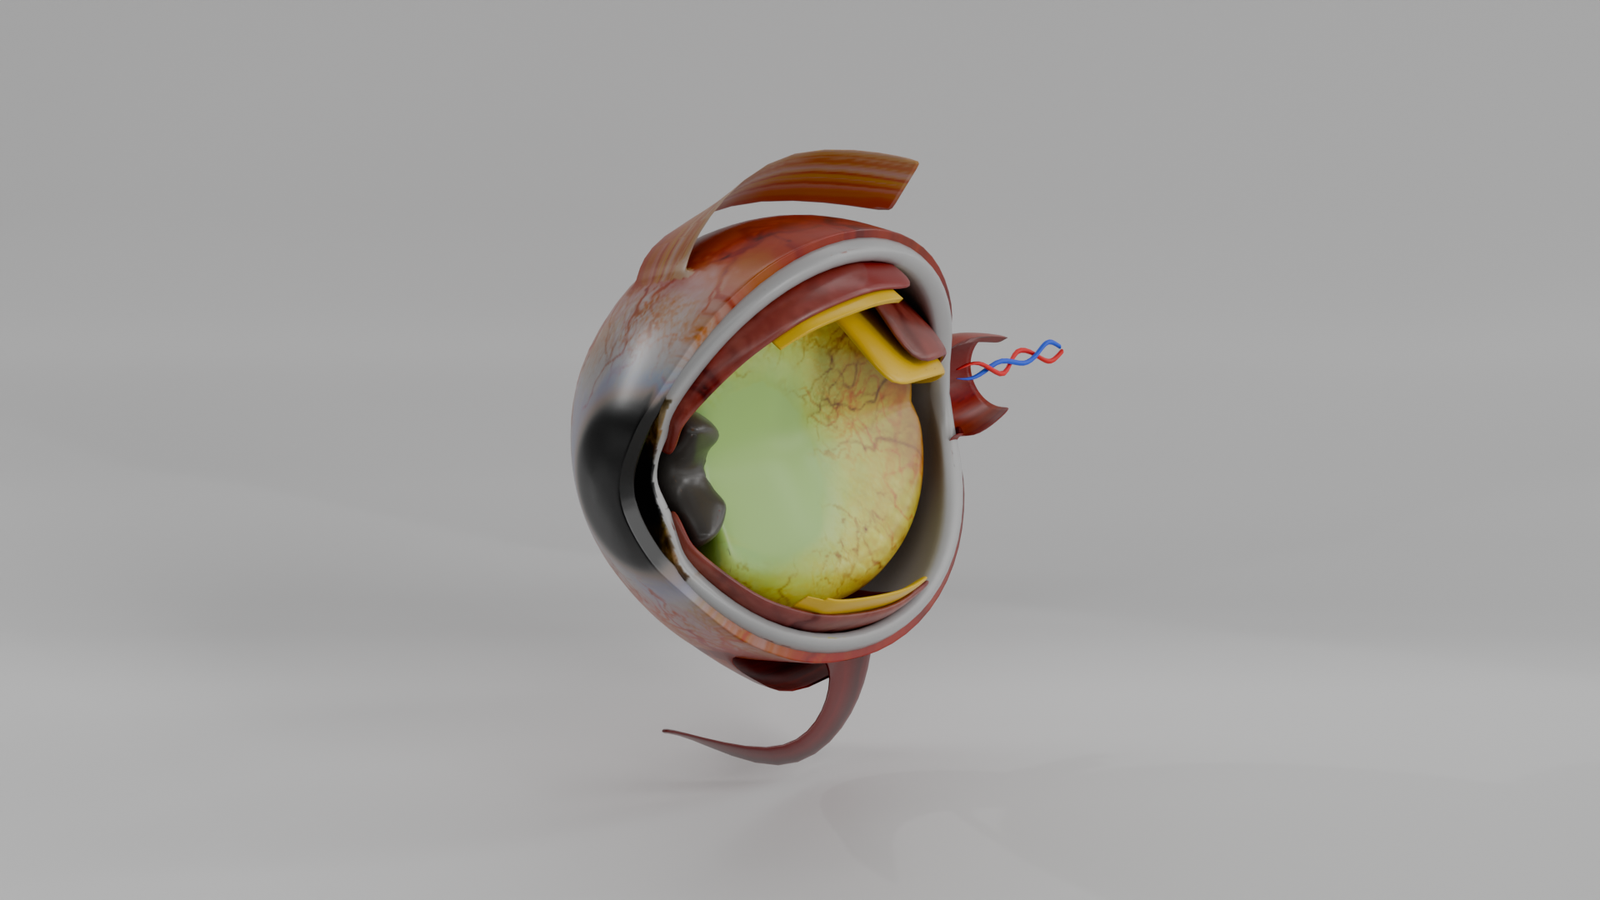

Ojo Humano

Modelo 3D educativo